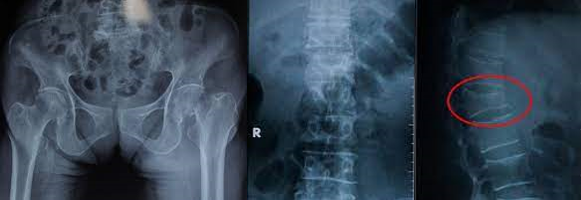

Xquang quy ước:

Hình ảnh đốt sống tăng thấu quang, biến dạng thân đốt sống, với các xương dài thường giảm độ dày vỏ xương.

- Trường hợp không có điều kiện đo mật độ xương: Có thể chẩn đoán xác định loãng xương khi đã có biến chứng gãy xương dựa vào triệu chứng lâm sàng và Xquang: Đau xương, đau lưng, gẫy xương sau chấn thương nhẹ, tuổi cao…